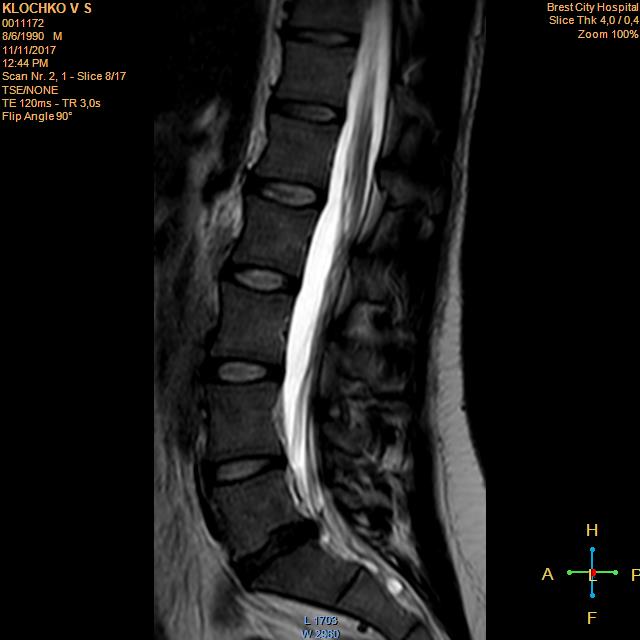

Тренировки с межпозвоночной грыжей.